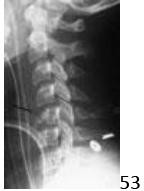

53 Which of the following best characterizes the injury shown in Figure 53?

DISCUSSION: The injury shown is a flexion compression injury also known as "tear drop" fracture. It is characterized by the large anteroinferior fragment

off the vertebral body and the retrolisthesis seen in this image. It is considered an unstable injury and should be distinguished from the more stable and minor extension tear drop avulsion where there is no vertebral malalignment and the anteroinferior fracture is a small avulsion of the annulus attachment. Other axial load injuries can be stable but have more of a compression or even burst pattern with loss of body height rather than the anteroinferior fragment. The radiograph does not demonstrate facet malalignment that would be seen with a facet dislocation. The Preferred Response to Question # 53 is 3.